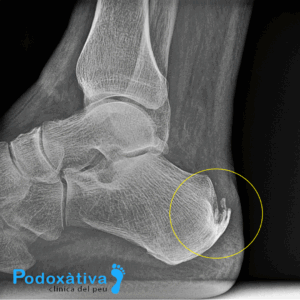

- Tendinitis de Aquiles: Se localiza en el tendón que une la zona del talón con los dos músculos de la pantorrilla. Esta tendinitis suele ser frecuente entre corredores, atletas o senderistas. El dolor se siente al caminar o ponerse de puntillas, debido a la tensión producida entre el tendón de Aquiles y la presión soportada por el talón

Otra de las lesiones es la fascitis plantar, que afecta al talón debido a una inflamación del tejido fibroso que unifica los dedos con el talón, atravesando la planta del pie. Esto genera un dolor punzante en dicha zona, especialmente durante los primeros pasos tras un largo reposo.